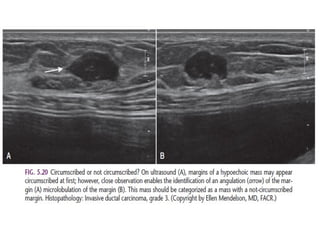

The margin of a lesion can be:

Circumscribed (historically well-defined This is a benign finding.

Obscured or partially obscured, when the margin is hidden by superimposed

fibroglandular tissue. Ultrasound can be helpful to define the margin better.

Microlobulated. This implies a suspicious finding.

Indistinct (historically ill-defined).

This is also a suspicious finding.

Spiculated with radiating lines from the mass is a very suspicious finding.